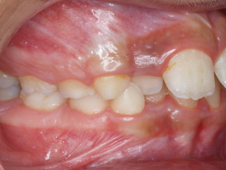

L’orthopédie dento-faciale a pour but de redonner une denture fonctionnelle et esthétique. Elle a aussi un rôle préventif. Des dents bien alignées sans encombrement ni mauvaise orientation rendent l’hygiène plus facile, limitant ainsi le risque de caries et les problèmes parodontaux. Un bon articulé dentaire permettra une bonne mastication, une bonne élocution et une bonne santé.

Les relations très étroites entre respiration, déglutition et phonation ne sont plus à démontrer. Si une de ces fonctions est entravée, une réaction en cascade dysfonctionnelle se met en place au niveau musculaire, dentaire et squelettique et aboutit à des problèmes au niveau des mâchoires.

Une prise en charge précoce peut donc s’avérer salutaire pour éviter que le trouble ne s’inscrive en dysfonction et aboutisse à des décalages squelettiques au niveau des mâchoires.

Si ces décalages osseux existent des appareils d’orthopédie peuvent être indiqués pour accélérer ou freiner la croissance et ainsi éviter un traitement chirurgical en fin de croissance ou chez l’adulte, lorsque la croissance n’est plus possible.